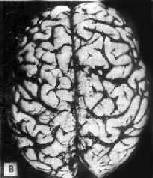

肉眼观,脑萎缩明显,脑回窄、脑沟宽,病变以额叶顶叶颞叶最显着(图16-32),脑切面可见代偿脑室扩张

初老期痴呆的脑 A

初老期痴呆的脑 B

图16-32 初老期痴呆的脑

示脑明显萎缩(A),与正常脑(B)的对比